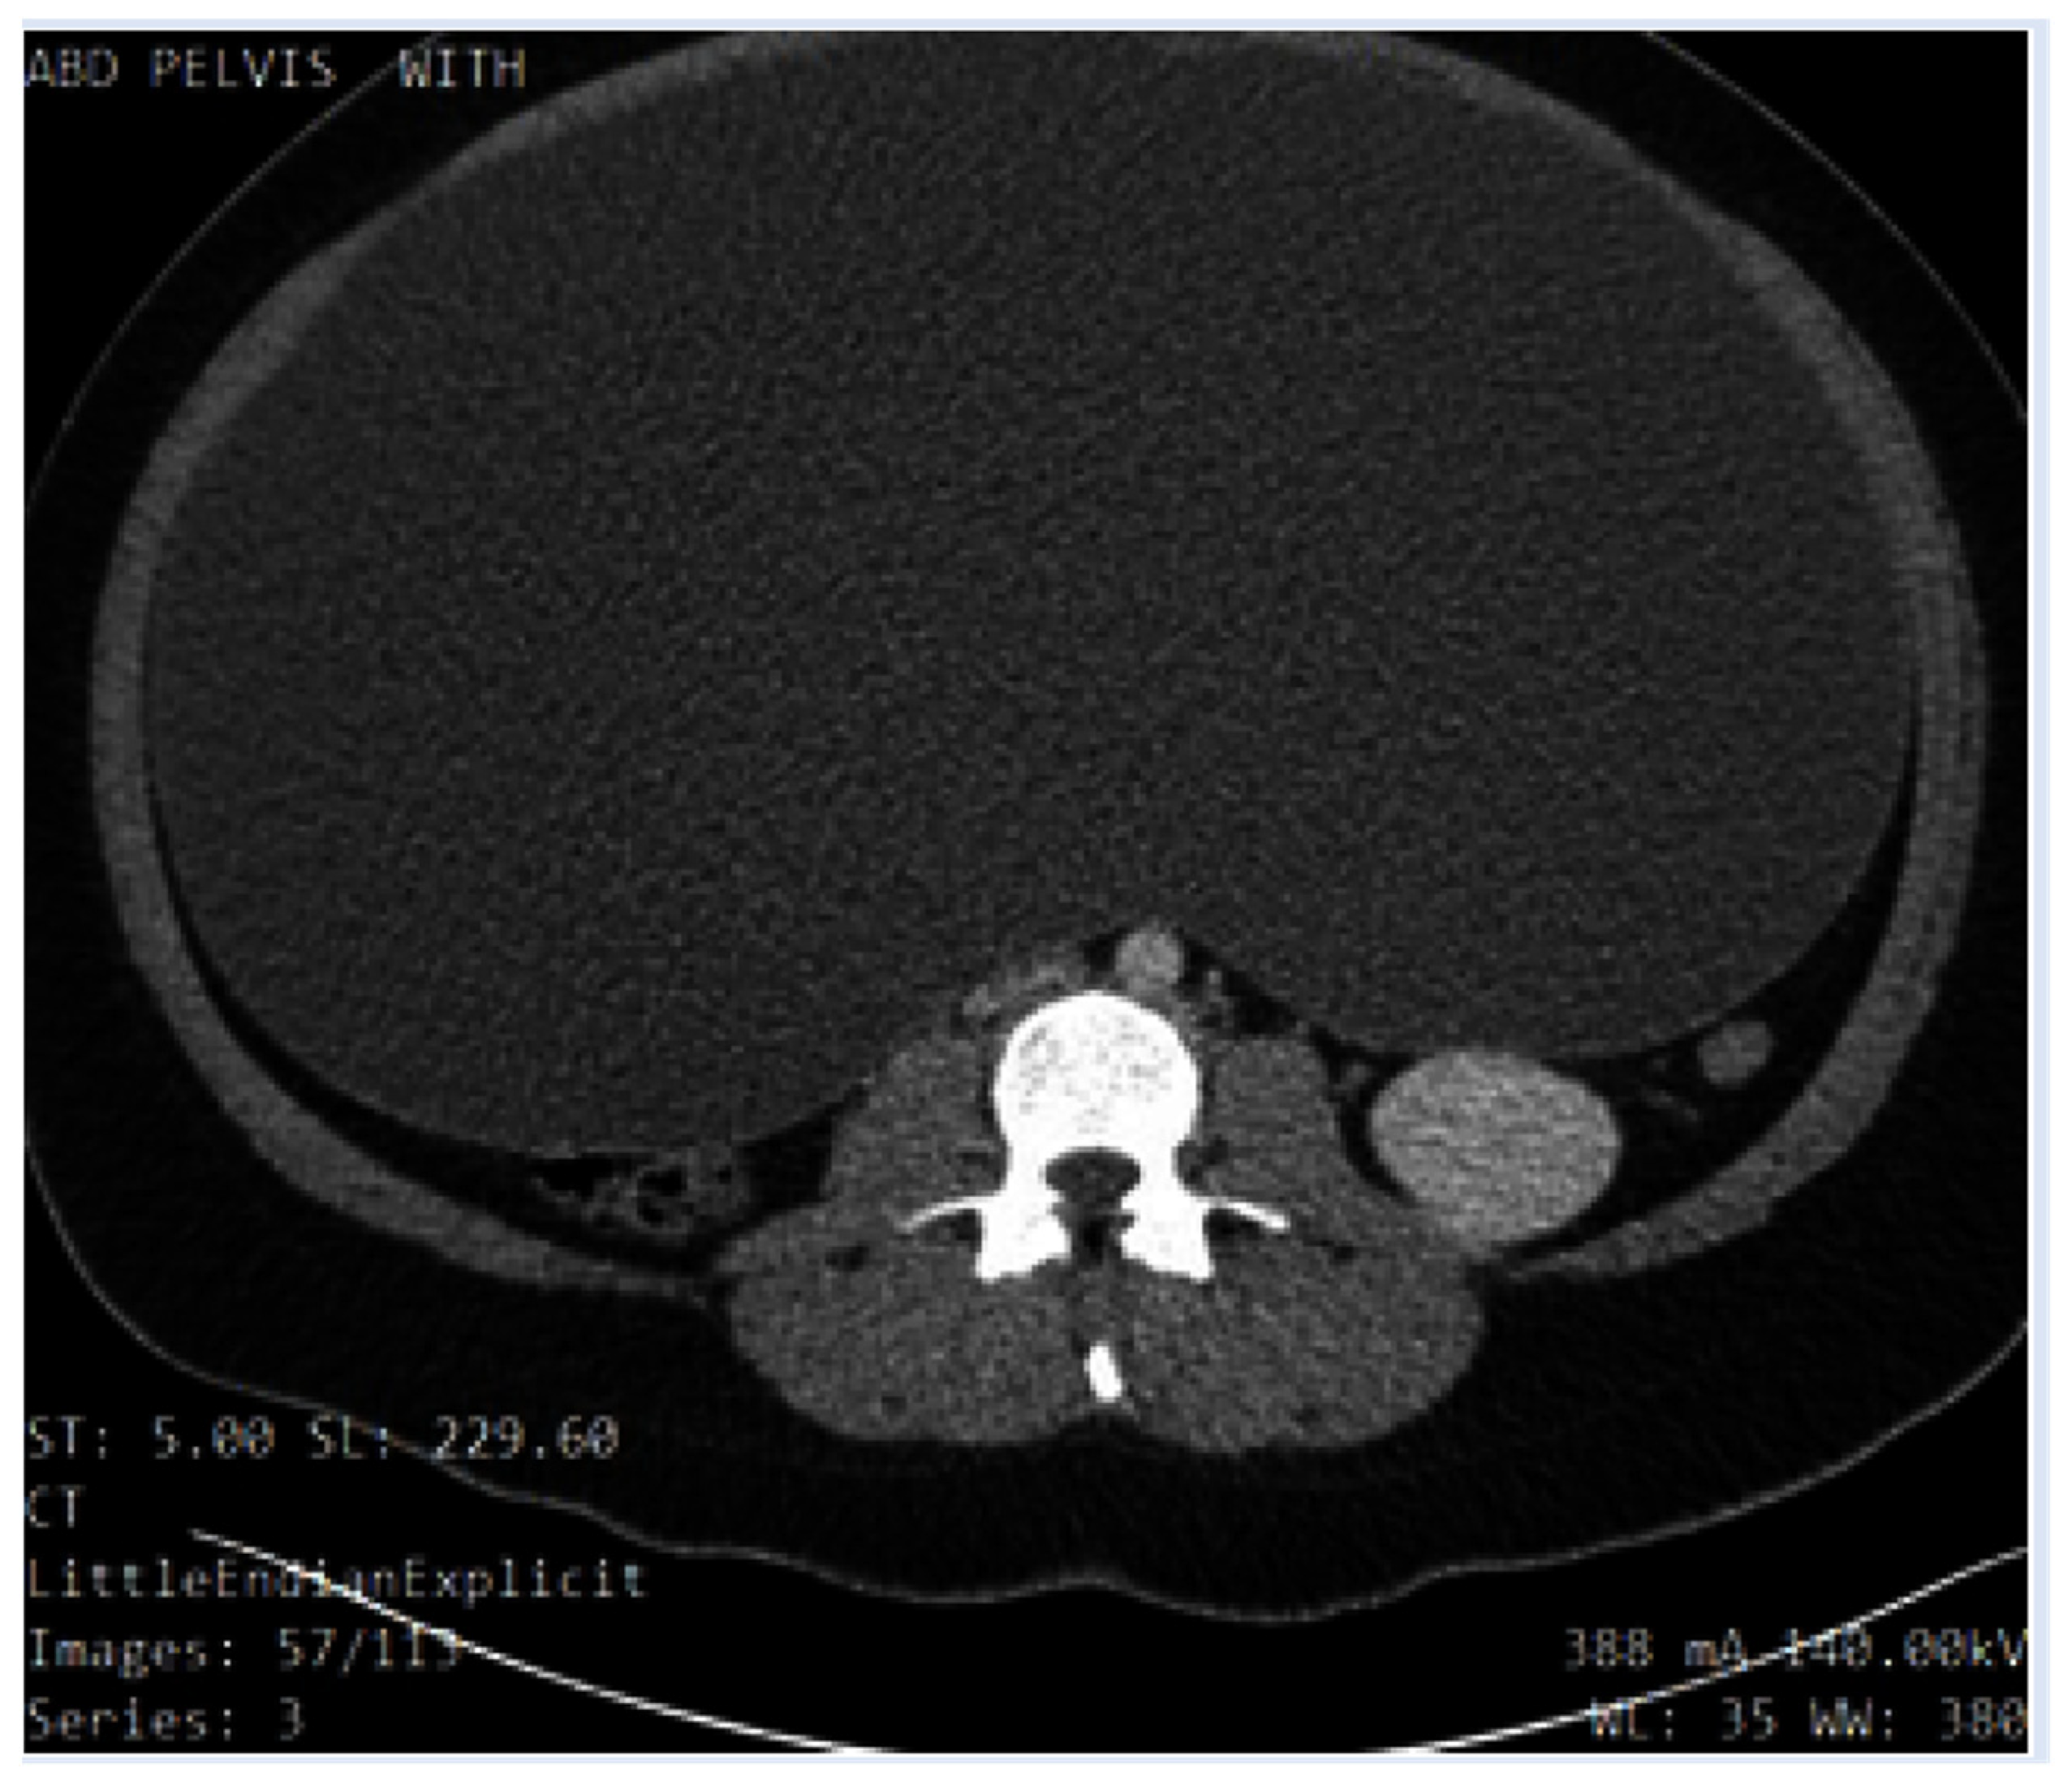

A pelvic ultrasound reported a normal uterus with no endometrial abnormalities, and the right ovary appeared normal. The left ovary was not visualized (Figure 1 and Figure 2). Additionally, the origin of the large cystic structure was unknown. An abdominal/pelvic computerized tomography (CT) with contrast found a 36 cm cyst lesion filling the abdominal and pelvic cavity which appeared to originate from the left adnexa with a complicated hyperdense fluid or debris focus inferiorly (Figure 3). The surrounding structures appeared unremarkable. There was a trace amount of fluid in the Douglas pouch (Figure 4).

Figure 3. Sagittal slice of the patient’s abdomen on non-contrast CT showing the cyst occupying most of the abdominal cavity. .